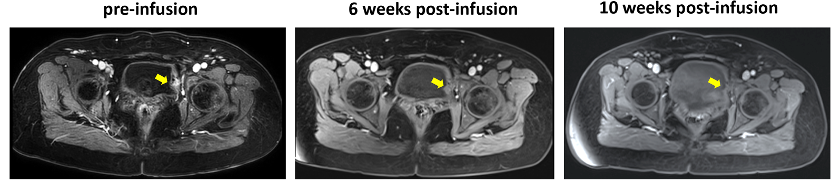

肿瘤浸润淋巴细胞(TIL)疗法在多种癌症的治疗中展现出令人鼓舞的结果。传统的淋巴细胞清除方案较为剧烈,是TIL更广泛应用的主要限制因素。改良的预处理策略可能减轻副作用,并证实肿瘤反应性T细胞在血液中的持续存在。有研究报道了新型预处理方案可以明显减轻患者副作用,并保持了TIL较好的治疗效果。该研究报道的是一例复发性宫颈癌伴膀胱转移的病例。患者没有接受常规使用的大剂量IL2处理,而是首先接受了为期 3 天的静脉环磷酰胺 (20 mg/kg) 治疗,间隔两天后再接受 TIL 静脉输注同时接收了半剂量(100 mg)的 PD-1 抗体治疗。TIL输注10周后,患者完全缓解(图1),不良反应可以忽略不计,无需重症监护室的干预。外周血细胞计数和TCR谱系测序显示,输注的TIL明显扩增和且能够长期持久存在(图2)。

图1.患者肿瘤情况